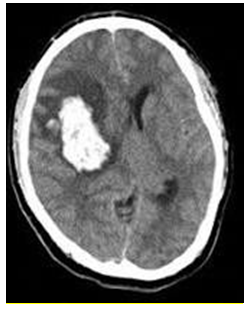

Homem de 65 anos apresenta queda da própria altura e é levado ao Pronto Atendimento. É portador de hipertensão arterial sistêmica e fibrilação atrial. Faz uso irregular de hidroclorotiazida, enalapril, anlodipino, clonidina e rivaroxabana. Ao exame físico, PA: 226X122mmHg, FC: 102bpm, FR: 22ipm. Apresenta-se sonolento, abre os olhos e verbaliza ao chamado e obedece aos comandos. Apresenta redução da força no dimidio esquerdo. Sem outras anormalidades.

Exames de laboratório: Hemoglobina 13,2g/dL; Leucócitos 11.630/mm³; Neutrófilos Segmentados: 8.548/mm³; Plaquetas 197.000/mm³; RNI 2,1; PTT 39s (controle 30s); Glicemia: 142mg/dL.

Tomografia computadorizada do crânio: